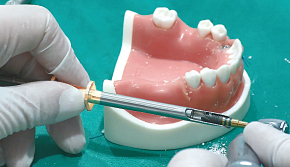

임플란트에 CowellBMP 코팅 시 : CowellBMP 용액을 원형 홈에 3~4방울 떨어트려서 임플란트에 코팅

1. Bone Carrier의 원형 홈에 먼저 rhBMP-2 용액을 주사

-

2. Hand-piece를 이용하여 원형 홈에 Fixture를 천천히 회전